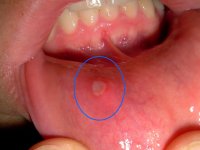

Ağızda çıkan bezelere dikkat!..